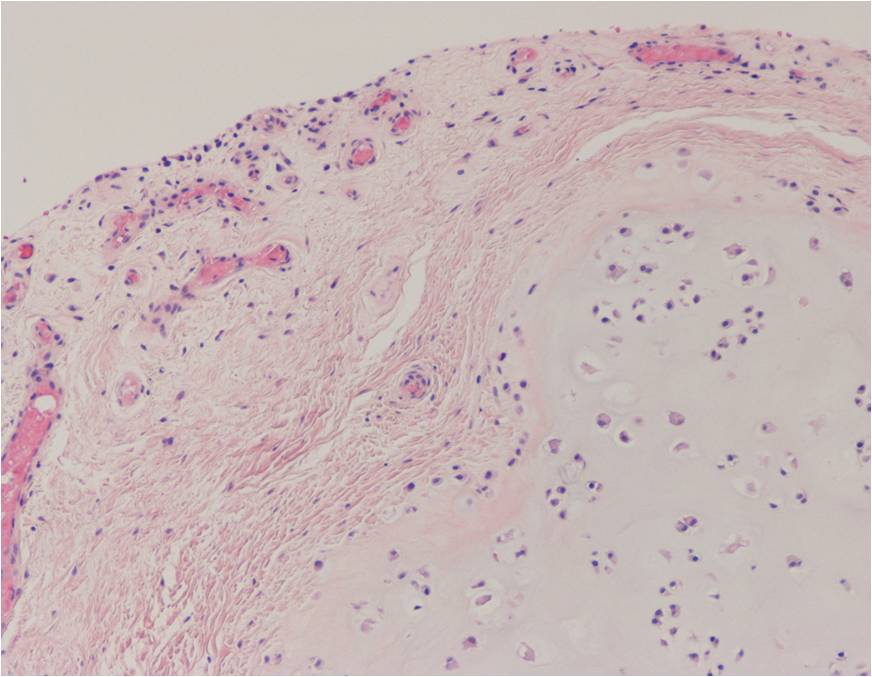

Synovial chondromatosis is an uncommon, benign, process that occurs in large joints, such as the knee (50%), hip, elbow, or shoulder. This process mainly affects synovium and hence most commonly arises from joints and tendons which are lined by synovium. Synovial Chondromatosis may also affect bursae and extend into surrounding soft tissues. This condition is seen in patients between 20 and 50 years of age and most commonly in men (male-female ratio of 2-4/1). The patient usually complains of pain, stiffness, crepitance, swelling, and joint locking. The knee is the most common site to be affected. Symptoms are long-standing and progressive. The plain x-ray may be normal (5 to 33%) or there may be small flecks of calcification (Fig. 1 & 2). On MRI the nodules of cartilage are easily seen. MR imaging may also show synovial thickening, joint erosions and intraarticular calcifications. The signal characteristics of these intraarticular bodies depend of their composition. If mineralization is not present the signal intensity follows the cartilage signal with intermediate signal on T1 images and high signal on T2 weighted MR images. Uniformly calcified bodies follows bone density on all sequences with bone marrow signal centrally and low signal peripherally (Fig. 3-5). Histologically the cartilage is arranged in nodules, which are quite cellular (Fig. 7-9). Synovial lining is present surrounding the cartilage nodules (Fig. 8). The cartilage nodules are often referred to as loose bodies however they are not really loose and embedded in the synovium lining. This is considered a metaplastic condition as opposed to a true neoplastic condition. Rarely it may turn into a malignancy usually a low grade chondrosarcoma. Malignant change is suggested by deep erosions into adjacent bone.

Fig. 7 – 9. Microscopic Pathology. Low (Fig. 7) and intermediate (Fig. 8 & 9) magnification demonstrates nodules of cartilage with high cellularity. Synovial lining is present surrounding the cartilage nodules.